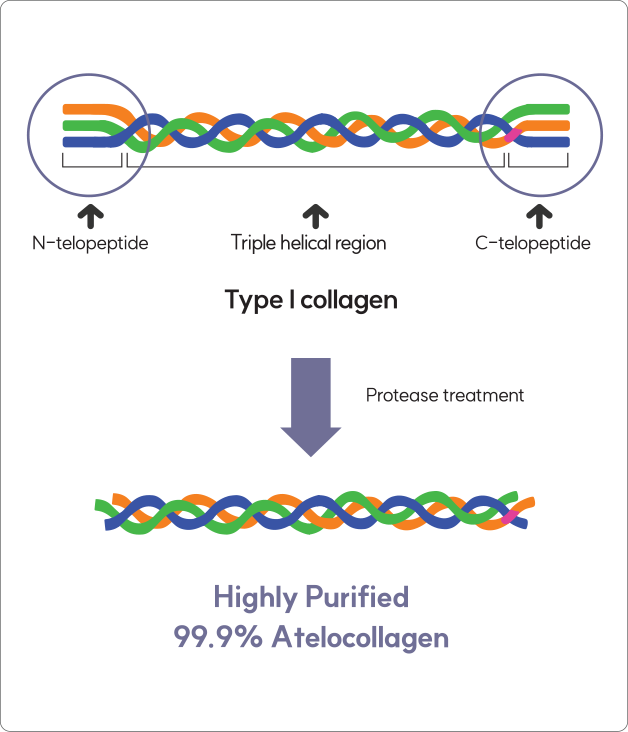

70% of Collagen Structure

Glycine, proline, and lysine account for approximately 70%

of the collagen structure. During fibroblast metabolic activity,

these amino acids stimulate fibroblasts to promote collagen

production and support collagen synthesis, helping improve

skin firmness and structural integrity.